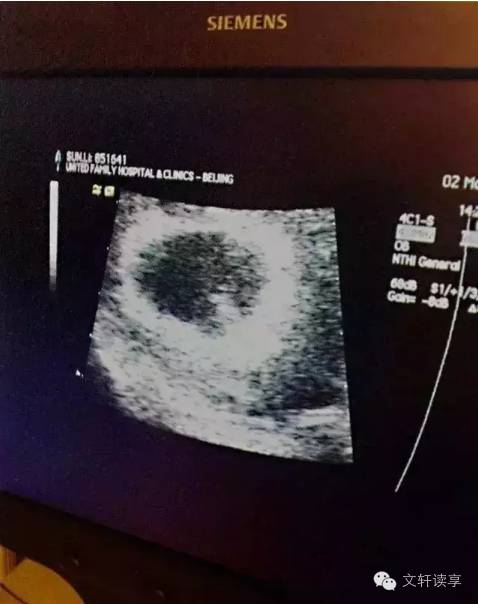

2013年,妹妹来了!

从此一家三口变成了一家四口,也多了一份牵挂!